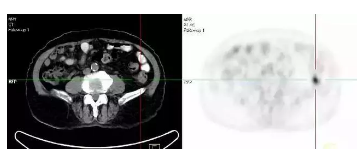

基于这一特性,用放射性核素标记的葡糖糖作为显像剂(即18F-FDG)注射到体内可使其在肿瘤等病变组织中浓聚,从而在图像中呈现出一个明亮的点,而这种浓聚点在PET-CT中用SUV最大值进行量化,它的全称为标准摄取值(StandardUptake Value ,SUV),是PET-CT在肿瘤诊断中常用的半定量指标,在评价疗效时的价值较大。

PET-CT(派特CT)是将PET与CT的信息结合到一起,保留了经典的解剖影像的作用,提高了病灶定位的准确性显像,就好像在坏人身上装上了一个GPS追踪器,无论他跑到哪里,都可以在茫茫人海中将其成功定位。